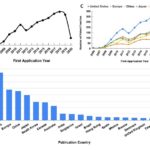

Global Patent Landscape of Induced Pluripotent Stem Cells

Review and analysis of worldwide patent literature regarding induced pluripotent stem cells.

Posted by John Lee on Thursday, May 20th, 2021 in May 2021, induced pluripotent stem cells, Intellectual Property, iPSC, Patent Landscape